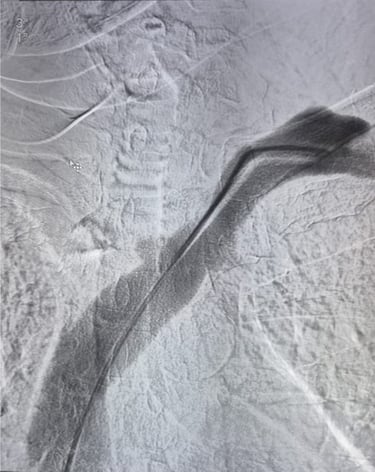

POST VENOPLASTY